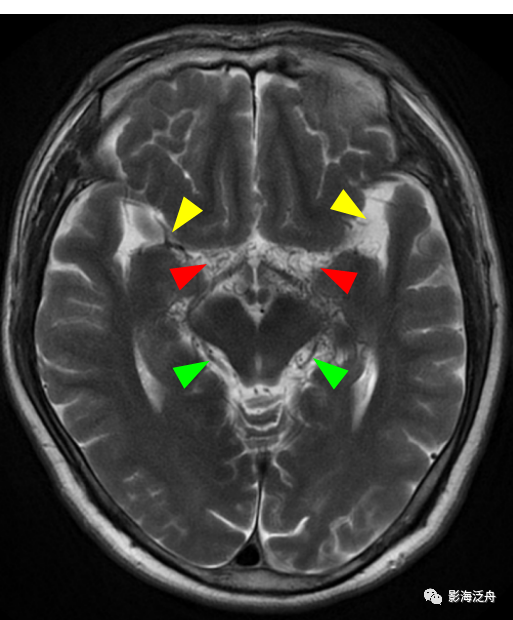

病例一:患者男,51岁,头晕1月余,神经系统查体无殊,血压正常。

病例一:烟雾病。如图所示,T2WI序列上在脑底池可以看到多发杂乱的细小流空血管影(红箭头),右侧侧裂池中大脑中动脉间断显示,且管腔粗细不均,而左侧大脑中动脉完全不显影(黄箭),两侧的大脑后动脉显示清晰(绿箭头)。脑底池中细小血管影增多的另一个常见原因多见于颅内感染,比如病毒性脑炎或隐球菌脑炎等。